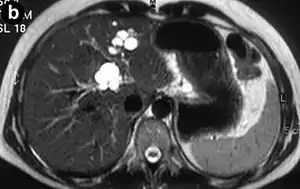

Bileduct dilatation in segment 5 arrow a,b) CT, c) MRI, d) MRCP

Magnetic resonance cholangiopancreatography (MRCP) of Caroli disease, showing cystic dilatations of bile ducts.[1]